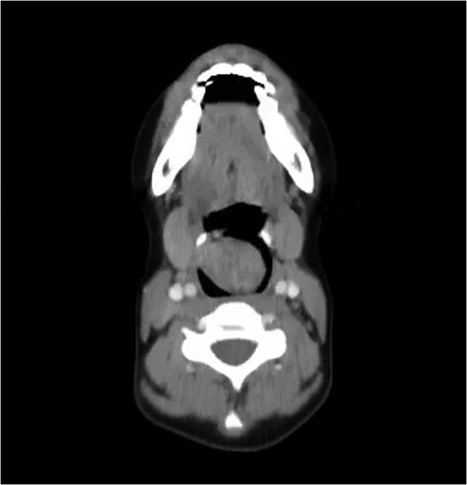

On examination, she was conscious, vitally stable and without any signs of respiratory distress. She was found to have a muffled voice while speaking. Upon inspection, using a tongue depressor, a part of a mass could be slightly visualized with gag reflex. Therefore, a consultation with the otolaryngology department was made for further evaluation. The patient underwent endoscopic laryngoscopy which revealed a large whitish mass that occupies the laryngeal inlet, blocking the view of the vocal cords. Computer tomography (CT) showed a well circumscribed (4 × 3 cm), low-attenuation, midline supraglottic mass, commencing just below the aryepiglottic folds and extending onto sclerotic arytenoids (Fig. 1).

CT of the neck with axial cut showing the schwannoma occupying the larynx.